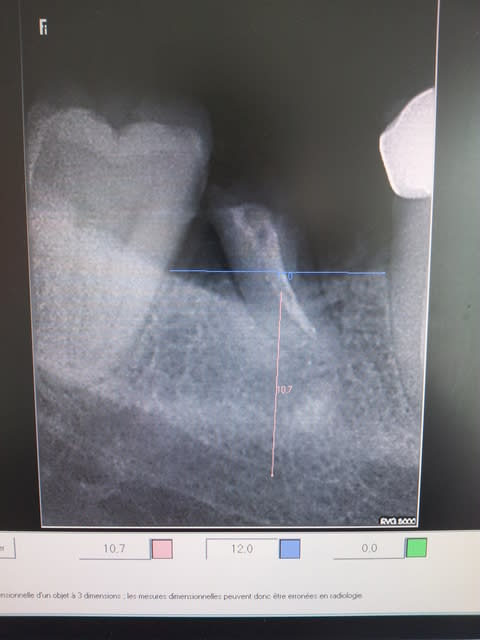

je pensais le cas assez simple...

voila la radio initiale que j'avais omis de poster..